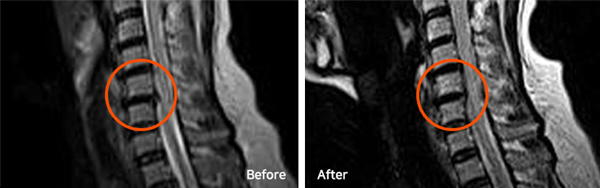

※ After 사진은 6개월 후 촬영된 모습으로, 파열된 디스크가 깨끗하게 흡수된 것을 확인할 수 있습니다. (치료기간-입원치료 4주, 외래치료 1개월 / ABCDE 복합 치료법)

파열된 목디스크는 치료를 잘 받으면서 충분한 휴식을 취하면 우리 몸으로 흡수되어 없어지는 경우가 많고, 파열이 심할수록 오히려 더 잘 흡수되기도 합니다.

단, 디스크로 다시 재흡수되는 것이 아니라 우리 몸의 대식세포 등이 튀어나온 디스크를 이물질로 인식해 녹여서 몸속으로 흡수되어 없어지는 것입니다.